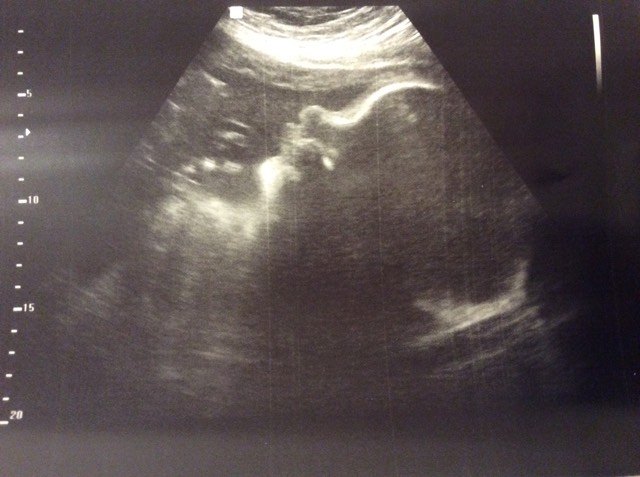

Over the years on here at Mommy Katie, we have added posts from outside contributors and expanded our audience by adding new content creators like last year when Estrella joined in and began taking over the YouTube channel. Well like many families, here at Mommy Katie we are constantly growing and with that we have added a new contributor who will be taking over the content geared at babies and new moms. This new contributor’s name is Heather and here in just a few short weeks, a baby girl named Zoey will also be joining us over here at Mommy Katie once she decides she is ready to come and join the rest of us in the world. For now, little Zoey is comfortable and growing, and Heather along with her husband and kids are preparing for her arrival.